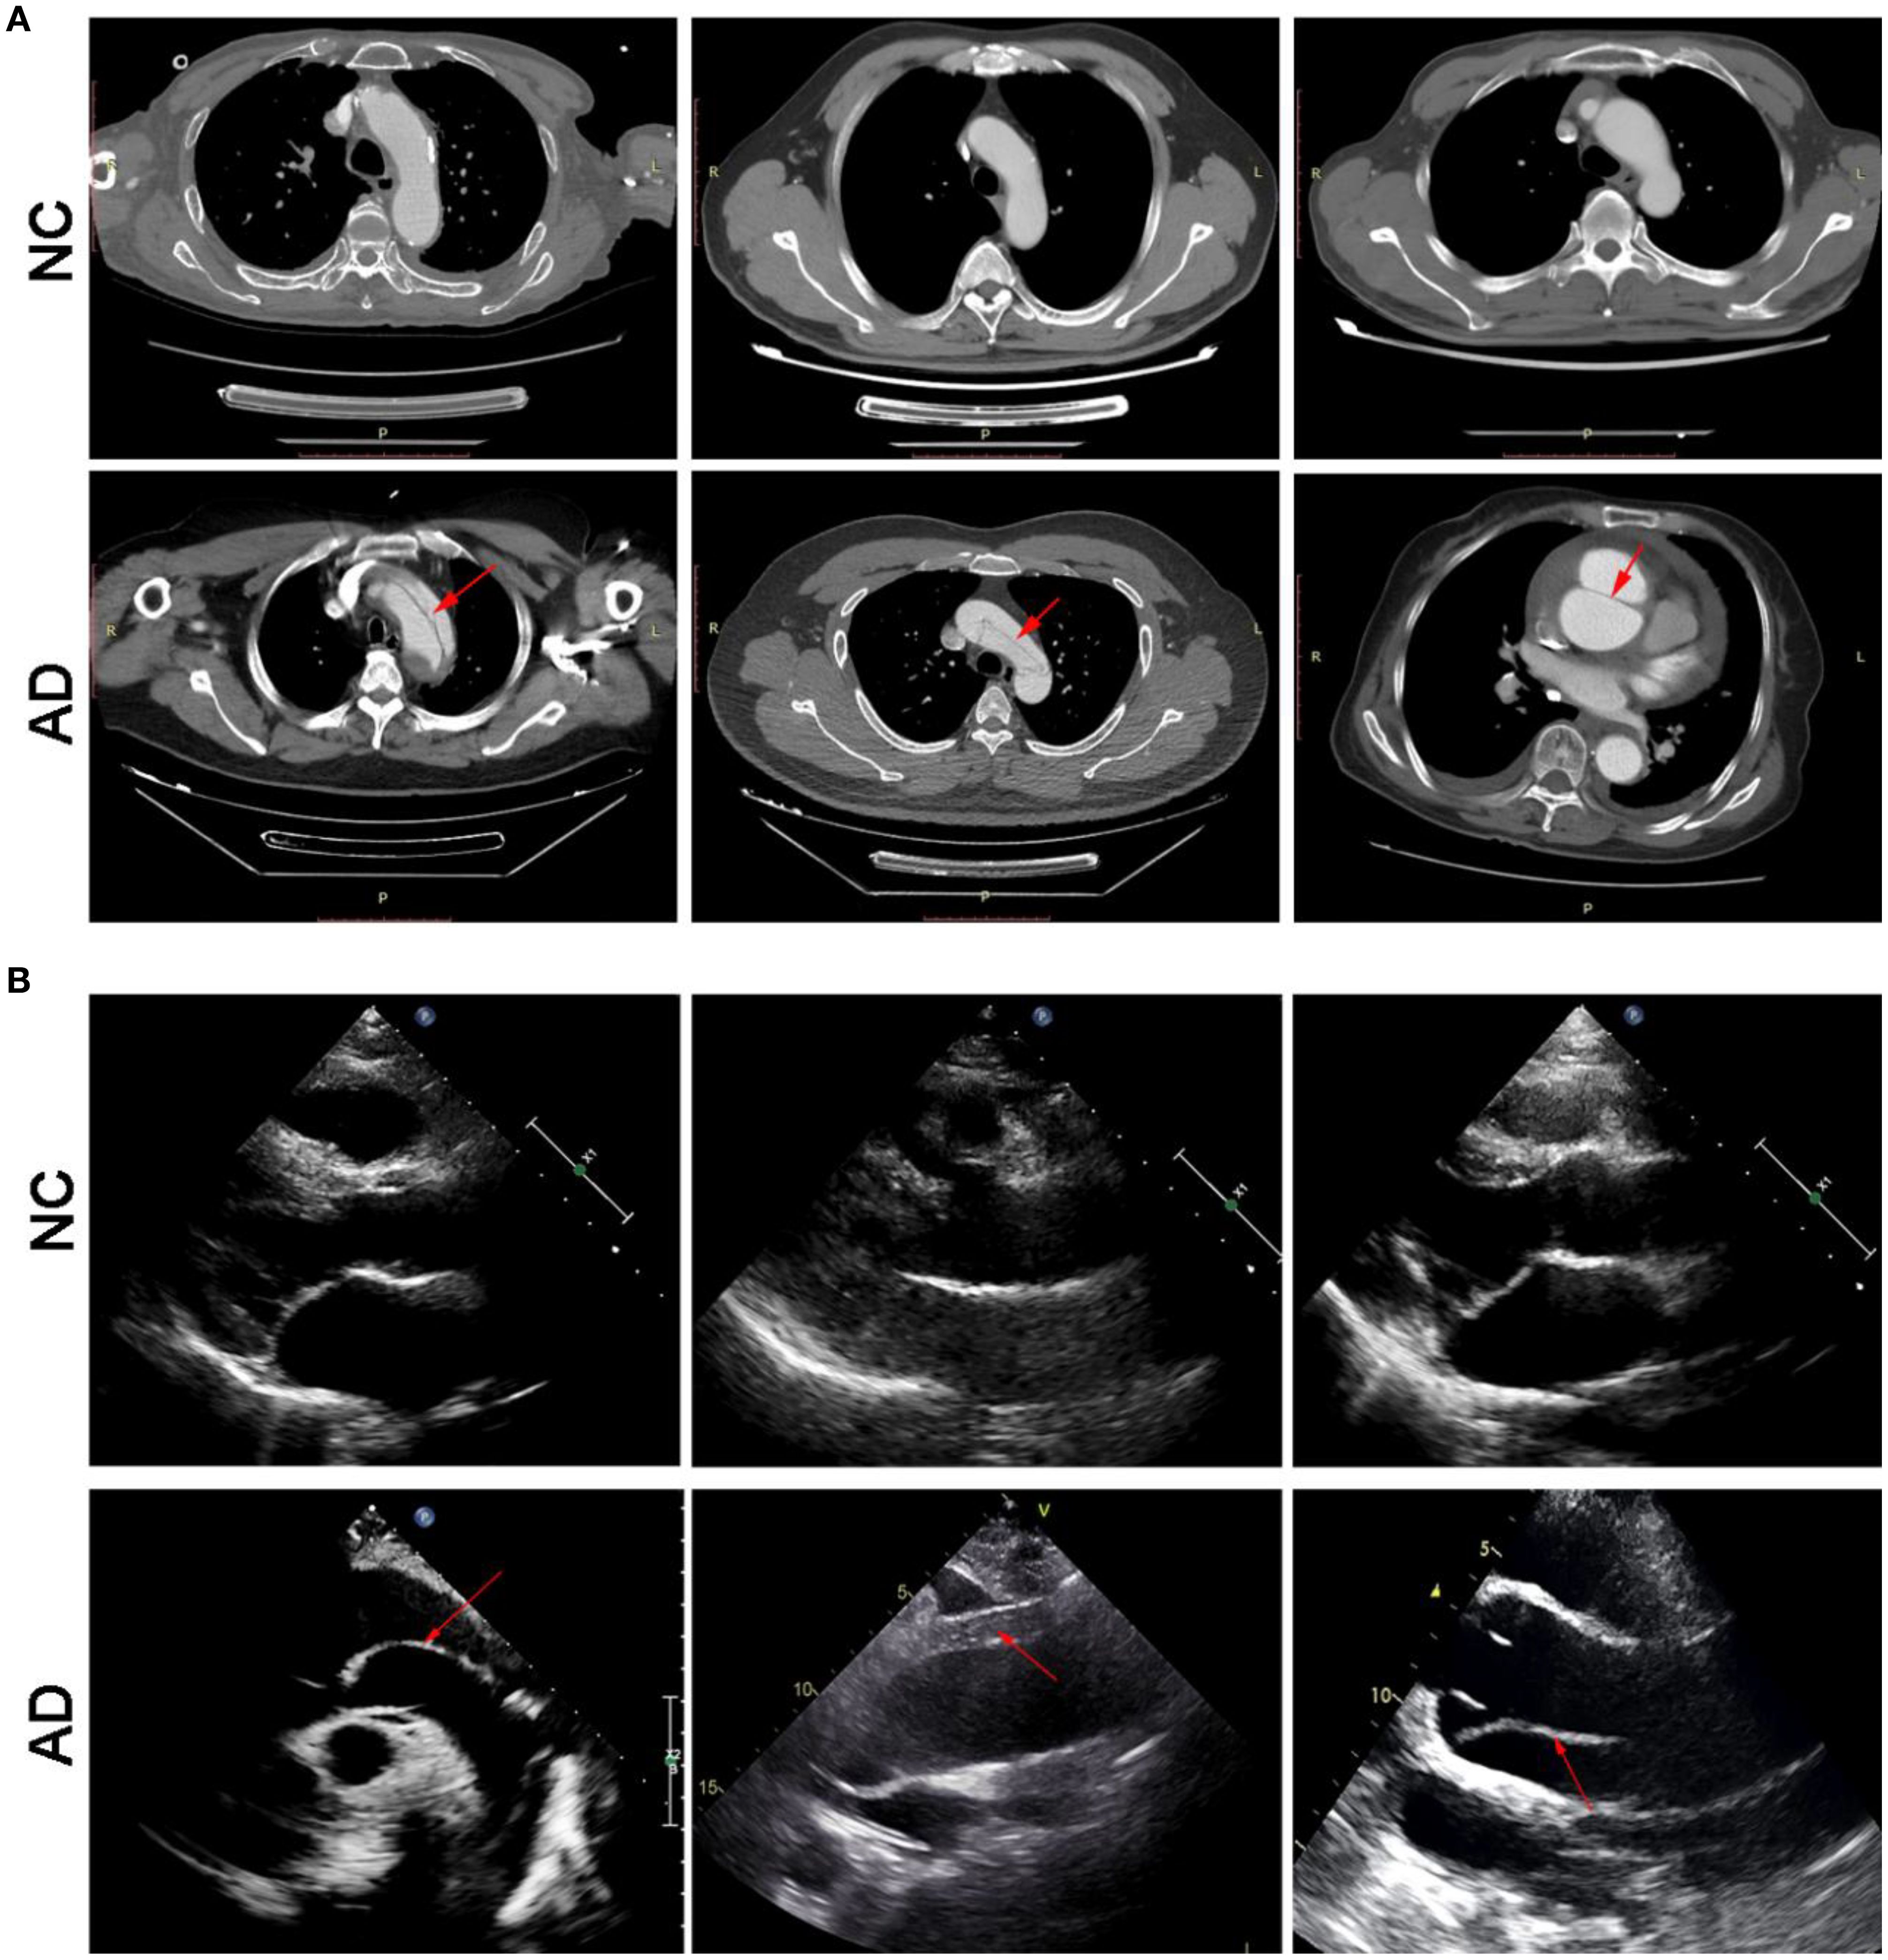

On enhanced computed tomography images, a linear low-density shadow (representing an intimal flap) can be visualized within the aortic lumen in patients with AD, which separates the aorta into true and false lumina (Figure 2A). In addition, the result of transthoracic echocardiography showed that aortic lumen of AD patients was widened, along with torn intimal echo in the lumen. These appeared as linear or strip-like structures that swayed throughout the cardiac cycle, dividing the lumen into true and false channels (Figure 2B). Notably, there was no occurrence of intestinal ischemia in any patient with AD (Supplementary Figure S1). However, these phenomena have not been observed in the NC group.

Figure 2

CT and ultrasound images showing comparative analyses. Panel A displays CT scans; the top row labeled “NC” shows normal conditions, while the bottom row labeled “AD” shows anomalies highlighted by red arrows. Panel B displays ultrasound images; the top row labeled “NC” shows normal conditions, while the bottom row labeled “AD” reveals anomalies highlighted by red arrows.

Figure 2. Transverse view of aortic computed tomography angiography (A), and transthoracic echocardiography (B).